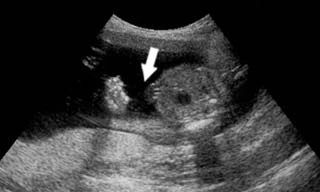

TPO - Cơ quan CSĐT Công an thành phố Bạc Liêu kết luận nguyên nhân khiến thai nhi 34 tuần tuổi tử vong khả năng do biến chứng của đái tháo đường thai kỳ.